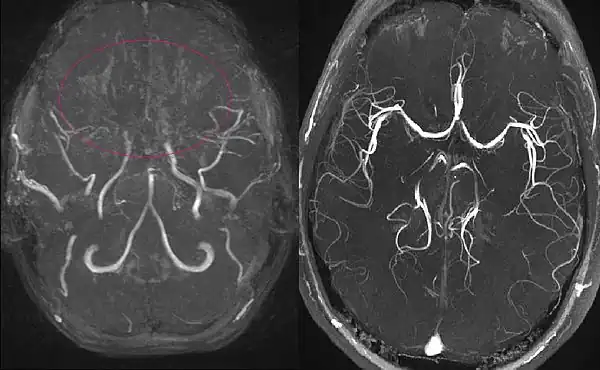

A ressonância magnética e a angiografia por RM podem demonstrar pequenas lesões subcorticais que são frequentemente indetectáveis na TC. A ressonância magnética e a angiografia provaram ser úteis porque a DMM envolve frequentemente enfartes pequenos e múltiplos. Essas modalidades de imagem permitem a visualização das porções distais ocluídas da ACI. Os vasos de Moyamoya aparecem como vasos finos incomuns na angiografia por RM ou como um vazio de sinal na imagem por RM. No entanto, tanto a imagem por RM como a angiografia por RM visualizam mal os vasos de moyamoya mais pequenos. A ressonância magnética pode ser usada como substituta da angiografia convencional em crianças, de acordo com os critérios diagnósticos da DMM (Tabelas 1 e 2), se a oclusão for claramente observada bilateralmente.[91][82][92] A angiografia por ressonância magnética pode detectar algumas lesões não observadas na RM, mas muitas vezes superestima a extensão da lesão. O aumento do sinal obtido com magnetos 3-T mais potentes fornece detalhes angiográficos significativamente maiores.[93] Além disso, a angiografia por RM pode ser usada no pós-operatório para determinar o estado do fluxo colateral e a patência dos enxertos de bypass extracraniano e intracraniano. A angiografia por ressonância magnética é limitada na resolução espacial e na avaliação da direcção do fluxo; embora esta última possa ser avaliada na angiografia por RM resolvida no tempo, esta técnica continua a sofrer de uma resolução espacial muito fraca.[94] Em termos gerais, a imagiologia por RM e a angiografia por RM são bons métodos para detectar a DMM, especialmente quando esta se encontra na fase 3 ou 4, mas não são muito eficazes como meio de estadiamento da doença.[95]

A angiografia por ressonância magnética (RM) e a angiografia por tomografia computorizada são métodos de diagnóstico não invasivos. As imagens de RM de alta resolução da parede do vaso também ajudam a diagnosticar a DMM, revelando um estreitamento concêntrico da parede do vaso com colaterais basais. A doença de Moyamoya (DMM), significa uma "nuvem de fumo" em japonês, também designada por oclusão espontânea do círculo de Willis, é uma doença cerebrovascular oclusiva crónica de etiologia desconhecida, caracterizada por alterações estenooclusivas na porção terminal da artéria carótida interna (ACI) e por uma rede vascular anormal na base do cérebro.[1] Tendo em conta o número crescente de doentes com envolvimento unilateral,[2] bem como a evidência de que um número substancial de casos unilaterais progride para uma apresentação bilateral,[3][4] os critérios de diagnóstico para a DMM definitiva foram revistos de modo a incluir doentes com apresentação bilateral e unilateral de estenose da ACI terminal com uma rede vascular anormal na base do cérebro (declaração do Comité de Investigação da DMM do Ministério da Saúde, Trabalho e Bem-Estar do Japão em 2015). Os critérios de diagnóstico também indicam que o diagnóstico definitivo da DMM requer uma angiografia por cateter nos casos unilaterais, ao passo que os casos bilaterais podem ser prontamente diagnosticados quer por angiografia por cateter quer por ressonância magnética/angiografia (RM/ARM). Quando há doenças causadoras ou condições associadas, termos como síndrome de moyamoya e moyamoya angiográfica são freqüentemente usados.[5] Embora incomum, a DMM é uma importante causa de doença arterial intracraniana não aterosclerótica, especialmente nos países do leste asiático. Nessas regiões, a estenose isolada da artéria cerebral média é observada em pacientes jovens, com eventual evolução para DMM.[6] A DMM é a causa mais importante de AVC ou ataque isquémico transitório (AIT) em crianças nesta parte do mundo.